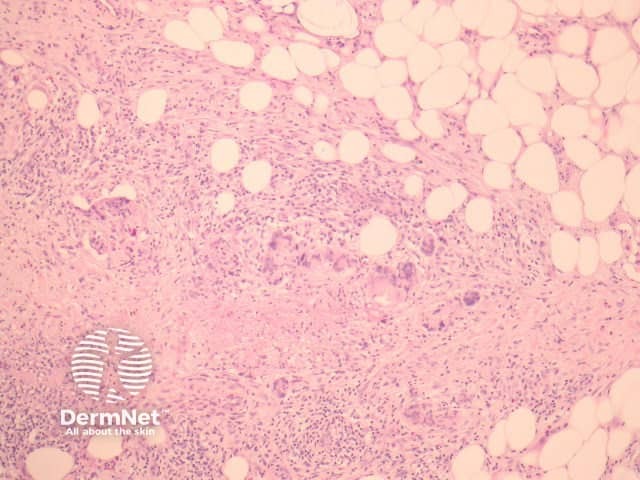

Erythema nodosum histologically represents the prototype of a septal panniculitis. The classic histopathologic presentation of erythema nodosum is that of a septal panniculitis with a mixed cellular infiltrate of lymphocytes, histiocytes, giant cells, and occasional eosinophils and a characteristic absence of vasculitis (figures 1-3).

Early lesions may be difficult to diagnose on histopathologic features alone. Sections may show oedematous septa containing a prominent mixed inflammatory infiltrate, and minimal fibrosis. As the lesions evolve, there is neutrophilic infiltration followed by chronic infiltrates, granulomas and septal fibrosis.

Small vessel vasculitis (or venulitis) may be seen in early lesions.

Figure 2